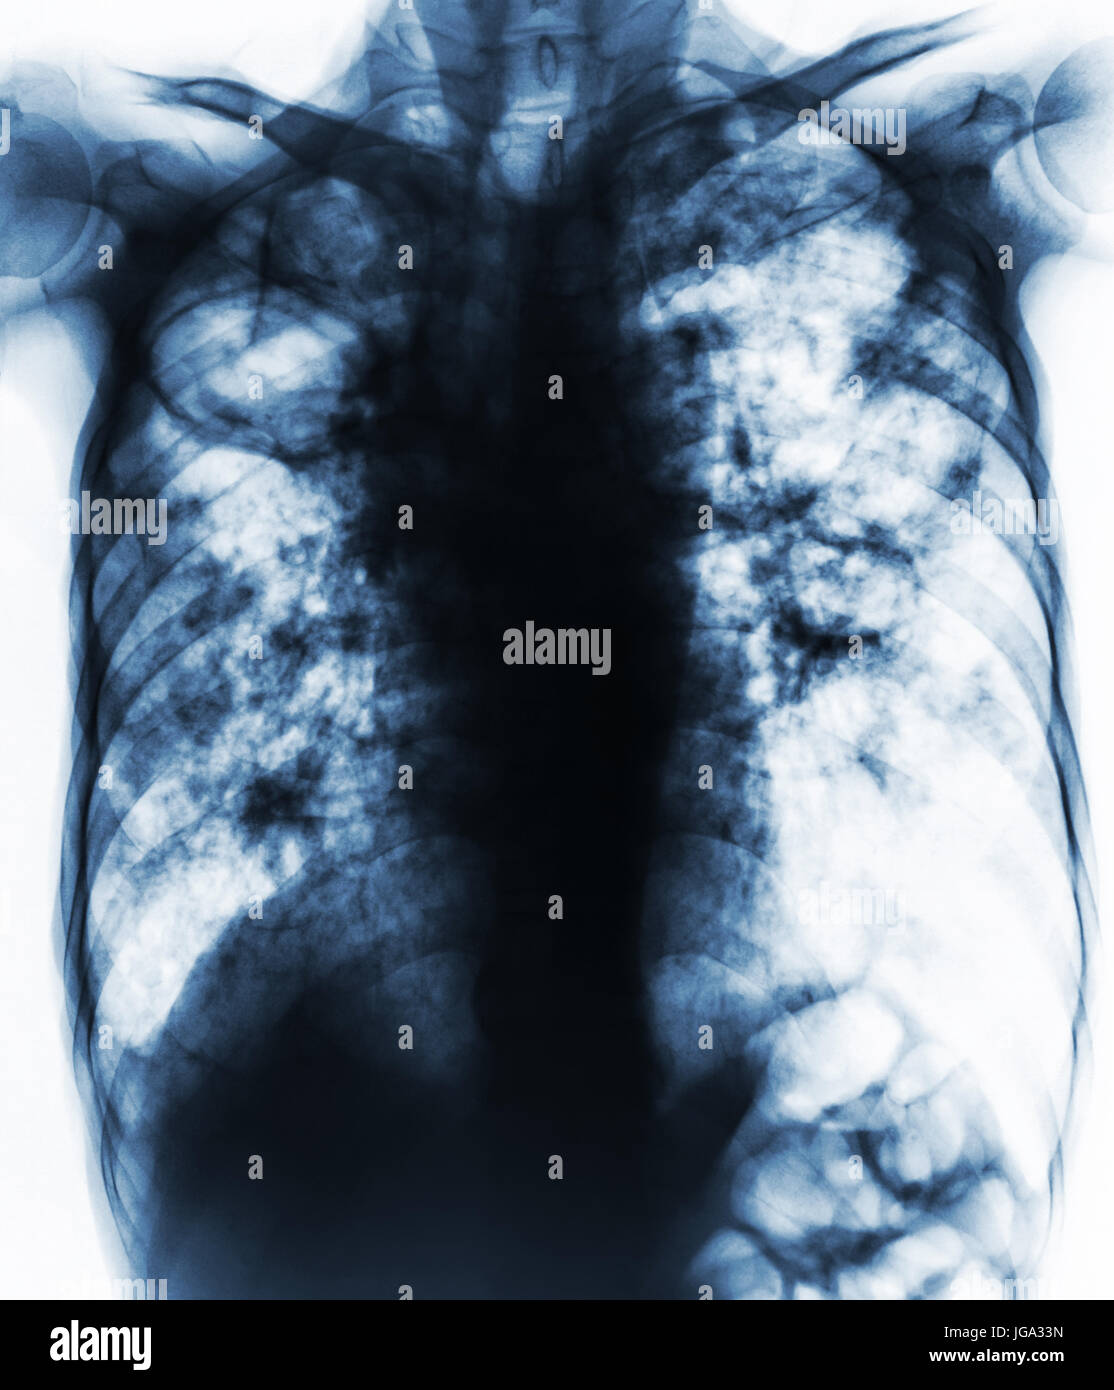

Chest Xrays Show Advanced Pulmonary Tuberculosis. Stock Image Image of finger, rays 259073781 Do Chest X Rays Show Tb The only sign that you have a tb infection is a positive tb skin test or blood test. A positive result from a tb blood test or tb skin test usually means tb infection. Prompt diagnosis of active tb. More tests, such as a chest radiograph, are needed to rule out tb disease. In 2022, approximately 7.5 million individuals became. Do Chest X Rays Show Tb.

From www.dreamstime.com

Chest Xrays Show Advanced Pulmonary Tuberculosis. Stock Photo Image of show, advanced 259073812 Do Chest X Rays Show Tb In 2022, approximately 7.5 million individuals became ill with tuberculosis (tb) and 1.5 million died. The only sign that you have a tb infection is a positive tb skin test or blood test. Prompt diagnosis of active tb. Negative tb blood test or tb skin test result, but you have symptoms of active tb disease. More tests, such as a. Do Chest X Rays Show Tb.